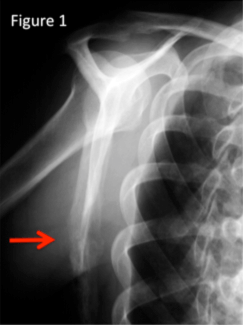

After the lungs and the liver, bone is the third most common organ affected by metastatic disease. Pain related to bone metastases can substantially lower patients’ quality of life. Patients with prostate and breast cancer in particular can suffer for years from pain and disability caused by bone metastases.